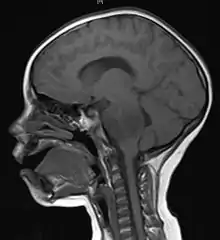

Imaging

Medical imaging plays a central role in the diagnosis of brain tumors. Early imaging methods – invasive and sometimes dangerous – such as pneumoencephalography and cerebral angiography have been abandoned in favor of non-invasive, high-resolution techniques, especially magnetic resonance imaging (MRI) and computed tomography (CT) scans,[37] though MRI is typically the reference standard used.[39] Neoplasms will often show as differently colored masses (also referred to as processes) in CT or MRI results.